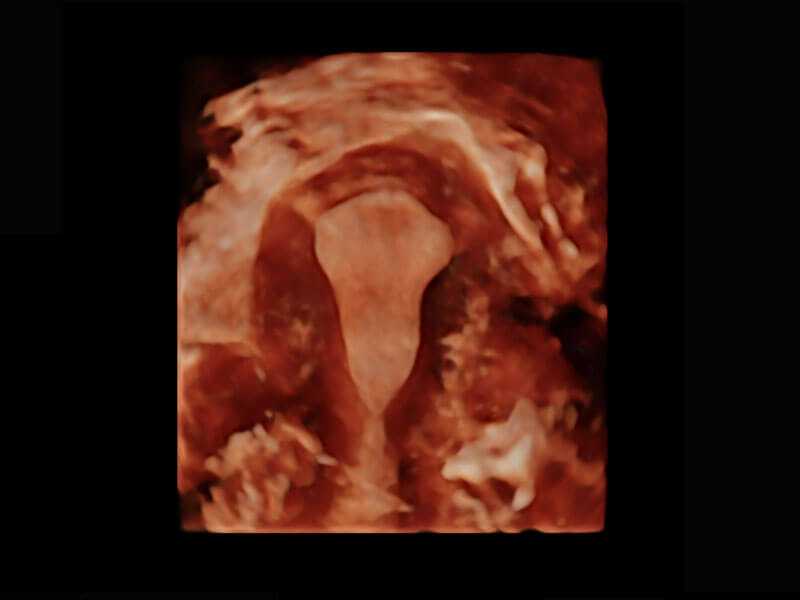

胎心筛查

P60搭载一系列胎儿心脏成像技术,实现精细的胎儿心脏评估。

• 四腔切面

• 四腔心血流

• 右室双出口

• 胎心容积成像